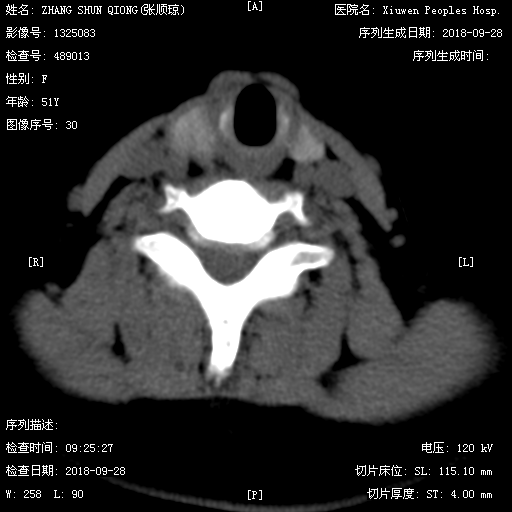

超声 CT平扫

CT表现:甲状腺右侧椭圆形低密度影,平扫低密度,增强动脉期轻度磨玻璃样强化,静脉期强化程度低于周围甲状腺实质,病灶范围较平扫缩小,边界变模糊。结合超声,定性恶性,倾向甲状腺髓样癌。

CT四大主征:1.低强化、2.钙化、3.形态规则、4.甲状腺中上极。